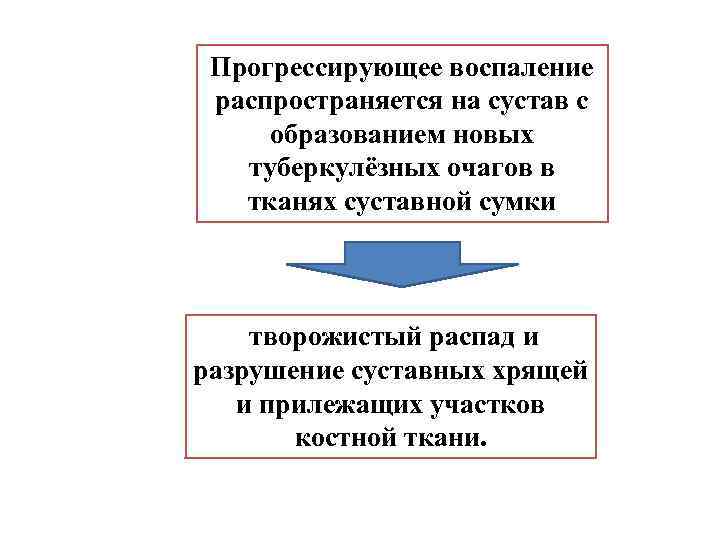

Прогрессирующее воспаление распространяется на сустав с образованием новых туберкулёзных очагов в тканях суставной сумки творожистый распад и разрушение суставных хрящей и прилежащих участков костной ткани.

Прогрессирующее воспаление распространяется на сустав с образованием новых туберкулёзных очагов в тканях суставной сумки творожистый распад и разрушение суставных хрящей и прилежащих участков костной ткани.